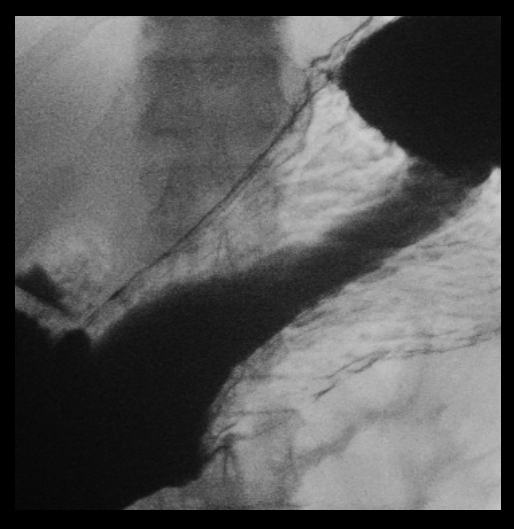

透視造影検査は、X線を使って体の中をリアルタイムで観察することができる検査です。

バリウムなどの造影剤を使用して、食道・胃・腸・尿路などの通り道や動きを詳しく調べることができます。当院では主に胃・大腸の検査や、整形外科での骨の整復などに活用しています。

胃のバリウム検査では、バリウムと発泡剤を飲んでいただき、胃の形状や動き、粘膜の状態を観察します。がんや潰瘍、ポリープなどの異常を発見することが可能です。